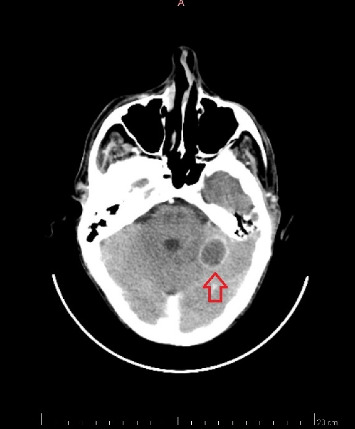

侵袭性毛霉病是一种侵袭性真菌感染,其特点是进展迅速,主要影响免疫功能低下的个体。在此,我们报告一例脾梗死合并胃肠道瘘和脑脓肿的病例,这是一种罕见的毛霉病活检的表现,在一名56岁的急性髓性白血病患者中得到证实。患者最初就诊时有3周的发热、盗汗和不适病史。考虑到胸部计算机断层扫描结果与真菌疾病和中性粒细胞减少症相符,他接受了广谱抗真菌治疗。在发生脾梗死和胃瘘后,患者接受了部分胃切除术和脾切除术。尽管采取了干预措施,但患者并没有取得成功的结果,并于术后第二天死亡。该病例强调了及时怀疑、立即抗真菌治疗和手术干预的重要性,以提高毛霉病多面表现患者的生存前景。

Invasive mucormycosis is an aggressive fungal infection characterized by rapid progression, primarily impacting immunocompromised individuals. Herein, we report a case of splenic infarction in association with gastrointestinal fistula and brain abscess as a rare presentation of mucormycosis biopsy, proven in a 56-year-old patient diagnosed with acute myeloid leukemia. The patient initially sought medical attention with a 3-week history of fever, night sweats, and malaise. Considering the chest computed tomography findings compatible with fungal disease and neutropenia, he underwent broad-spectrum antifungal therapy. Following the occurrence of splenic infarctions and a gastric fistula, the patient underwent a partial gastrectomy and splenectomy. Despite the interventions, the patient did not have a successful outcome and died on the second postoperative day. This case highlights the importance of timely suspicion, immediate antifungal therapy, and surgical intervention to improve the survival prospects of patients with multifaceted manifestations of mucormycosis.